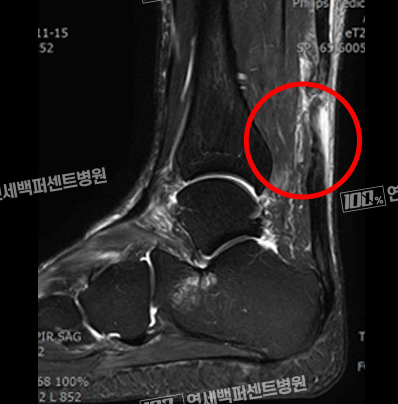

수술 전 MRI 영상

완전히 파열되어 절단된

아킬레스건